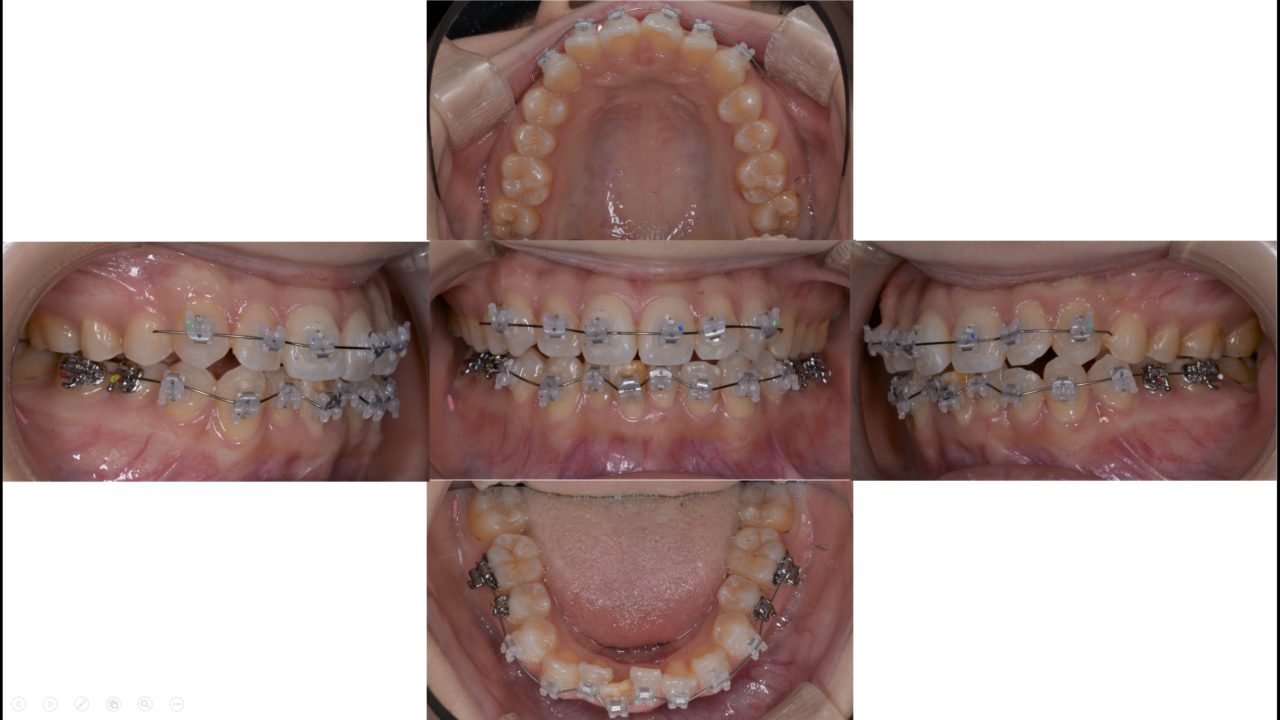

Before

| 診断 | 両側アングルクラスⅠ叢生 |

| 矯正方法 | 上下前歯だけ動かすマルチブラケットシステムを用いた部分矯正 |

| 矯正期間 | 3か月 |

| 備考 | 患者様は中学生の頃に矯正治療を経験されていましたが、保定装置(リテーナー)の使用を中断された結果、歯の凸凹(叢生)が再発していました。 また、右下中切歯(前歯)にはエナメル質形成不全が見られ、審美的な問題となっていました。 幸い、奥歯の噛み合わせ(臼歯関係)には問題がなかったため、前歯の歯並びのみを改善する部分矯正を適用しました。 その結果、わずか3ヶ月という短期間で治療を完了することができました。 矯正治療の終了後は、歯全体のホワイトニングを行い、特に審美障害のあった右下中切歯に対してダイレクトボンディングによる修復を行いました。 |